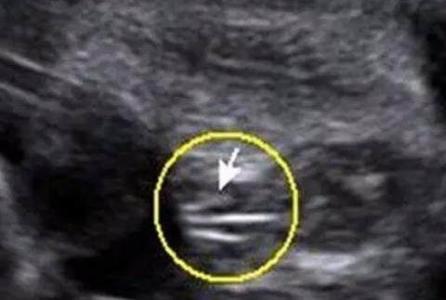

看到妊娠足月大小的腹部,毛愉燕医师也不禁咋舌。影像学检查提示李女士整个盆腹腔都已被肿瘤占据,子宫、双侧输卵管都被挤到了上腹部。不仅如此,结合妇检及临床表现,预计肌瘤的位置位于宫颈部位。

尽管已有心理准备,但是肌瘤拿出来的一刻,在场的医护人员还是惊叹不已:这个子宫肌瘤直径达37厘米,重量26斤,术中送去病理科快速冰冻检验,得用水桶运输。幸运的是,术中冰冻切片快速病理分析没有发现恶性成分。